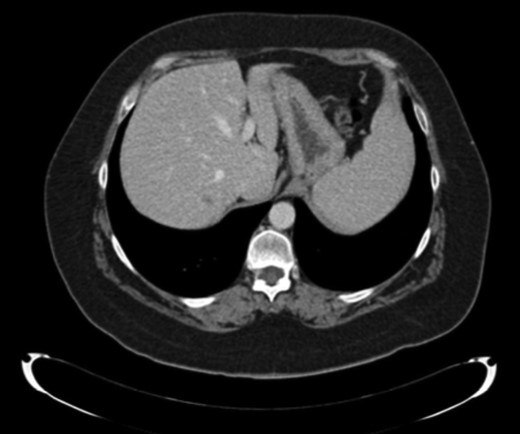

Finally, 12 months after this second liver surgery, a new hepatic lesion in left hepatic lobe of 3 cm was identified (Fig. 4). Systemic treatment was re-initiated with Cisplatin (75 mg/m2) and Cetuximab for 2 months. After that, left hepatectomy was performed with tumor-free surgical margins without subsequent complications. Surgical specimen revealed undifferentiated tumor.